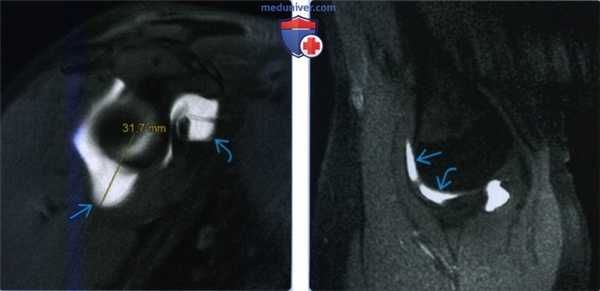

(Слева) На косой сагиттальной МР-артрограмме Т1ВИ FS y женщины 32 лет с разнонаправленной нестабильностью определяется растяжение нижней капсулы на 31,7 мм, превышающее норму в 24 мм. Кроме того, имеется сильное растяжение суставной капсулы около ротаторного интервала.

(Справа) На МР-артрограмме Т1ВИ FS с отведением и наружной ротацией у этого же пациента определяется симптом серпа с контрастом между передним пучком нижней суставно-плечевой связки и головкой плечевой кости. Кроме того, имеется симптом треугольника (треугольной пространство между нижней суставно-плечевой связкой, головкой плеча и суставной впадиной).